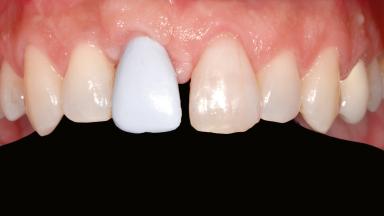

Staged bone augmentation of the alveolar ridge is indicated whenever a proposed implant site is deficient and will not support implant placement with simultaneous grafting. This is particularly true of healed sites presenting with facial flattening of the ridge. Since primary stability cannot possibly be achieved in this situation, it is recommended to use a staged approach with guided bone regeneration (GBR) for correct three-dimensional placement of the implant. In the anterior maxilla, staged GBR procedures are conducted not only to provide adequate bone volume for implant placement but also to restore a proper and stable contour of the orofacial ridge for improved long-term esthetics. A case is presented that demonstrates the technique for single-tooth replacement utilizing a staged approach with a particulate grafting material. A 50-year-old man whose tooth 11 was missing presented for consultation to the Center for Implant Dentistry in January 2010.

Prosthesis Type FDP

Defining Characteristics One missing tooth to be replaced by an implant-borne crown

Esthetic Risk High